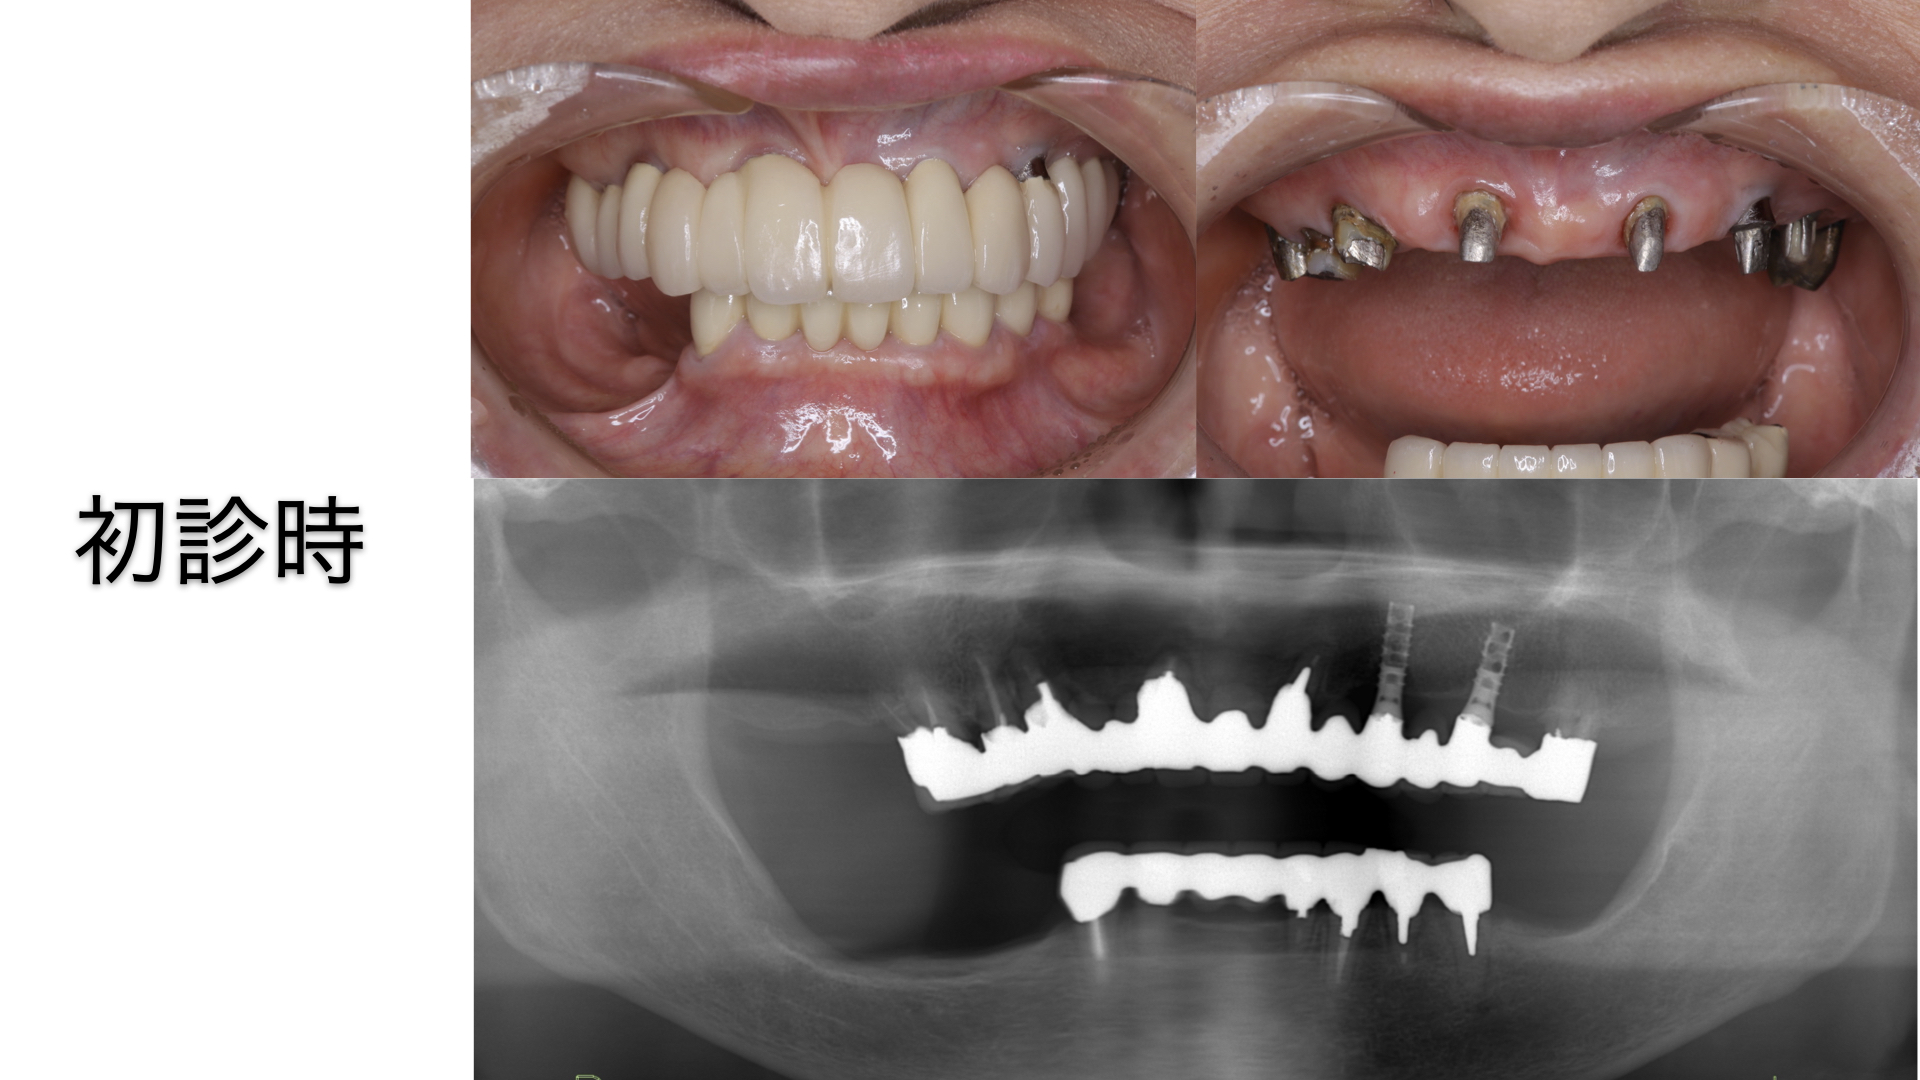

【初診時のお口の写真とレントゲン】

白い歯は装着されているが、歯の形も違和感があり、歯間ブラシも通らず、お掃除もできないセラミックが装着されていた。

レントゲン写真からは、ブリッジの土台となる歯の本数は少なく、さらに、重度の歯周病になっていることがわかった。